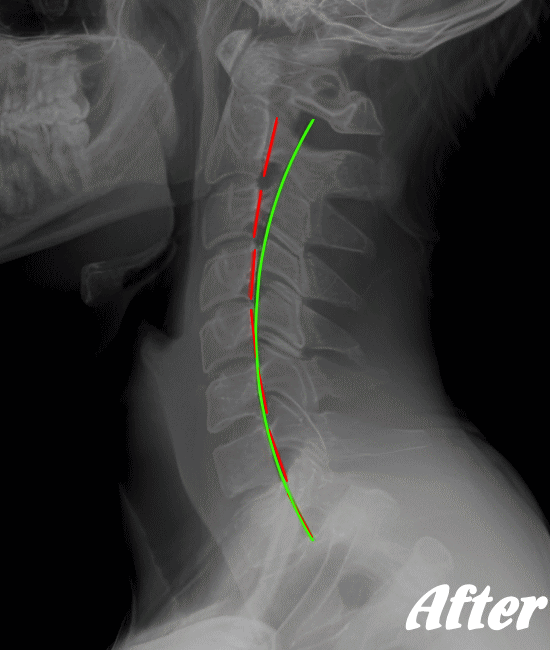

ストレートネックも、首に負担がかかりやすいので、注意が必要です。

HALOカイロプラクティック☆平和島整体院では、首の筋肉をゆるめていくため、まずは骨盤(特に仙腸関節)を調整、背骨(腰椎、胸椎、頚椎)を調整、そして肩甲胸郭を調整します。

そして、肩甲胸郭、つまり肩甲骨の動きをよくし、肋骨を広げ、丸まった背をのばし、胸が大きく広がるように調整します。肩甲骨には首の筋肉がつながっているので、調整は必須です。

状態に応じて、頭蓋骨を調整し、身体をリラックスさせます。基本的に、頚性神経筋症候群は姿勢の悪さに起因するところが大きいので、深く呼吸できる身体に改善していくことで、首のコリは取れていきます。